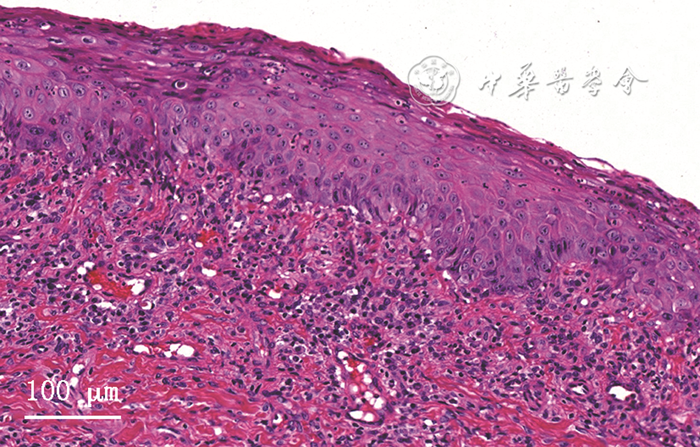

4.实验室检查:①行血常规、空腹血糖、糖化血红蛋白、凝血功能、感染性疾病标志物(乙肝、丙肝、梅毒、人类免疫缺陷病毒)以及大疱性疾病特异性抗体检测,结果示:糖化血红蛋白(7.2%)升高(正常值:4%~6%),余未见明显异常。②切取糜烂、白纹区及邻近外观正常的两块黏膜组织活检,其中一块组织(含糜烂、白纹区病损)行组织病理学检查示:黏膜上皮萎缩,灶区基底细胞液化变性,固有层淋巴细胞、浆细胞浸润(图2);另一块组织(仅含邻近病损外观正常的黏膜)行直接免疫荧光(direct immunofluorescence,DIF)检查示:基底膜区纤维蛋白原沉积,IgG(-),IgA(-),IgM(-),补体C3(-)。

▲ 图2 难治性口腔扁平苔藓患者病损区组织HE染色结果,示黏膜上皮萎缩,灶区基底细胞液化变性,固有层淋巴细胞、浆细胞浸润